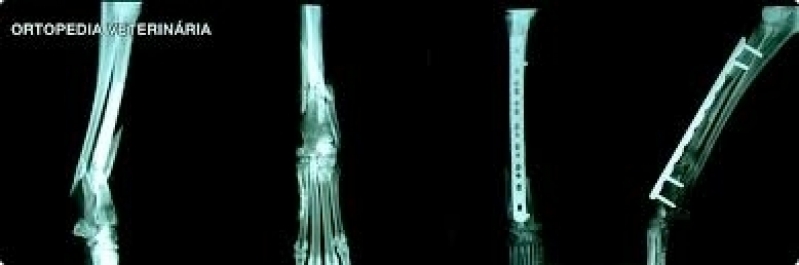

• Veterinários para animais exóticos;

• Veterinários para animais silvestres.